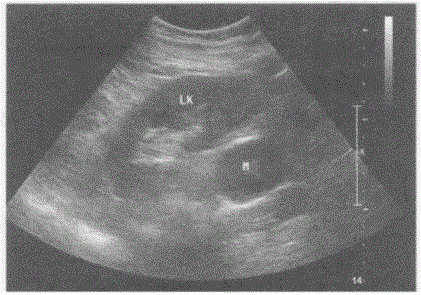

问题 临床资料:男,73岁,自述2年前体检发现左侧腹膜后肿物,大小4.3cm×3.0cm,此后多次复查肿物大小无明显变化。 超声综合描述:左肾下极与腹主动脉之间可见不均质低回声,与腹主动脉关系密切,边界清晰,形态规则,内可见形态不规则无回声,CDFI:其内及周边均未见动静脉血流信号。见下图及彩图55。 {图2} {图3} 超声提示:

选项 A.腹膜后囊实性占位(神经鞘瘤) B.腹腔囊实性占位 C.左肾囊实性占位 D.左肾上腺囊实性占位(嗜铬细胞瘤)

答案 A